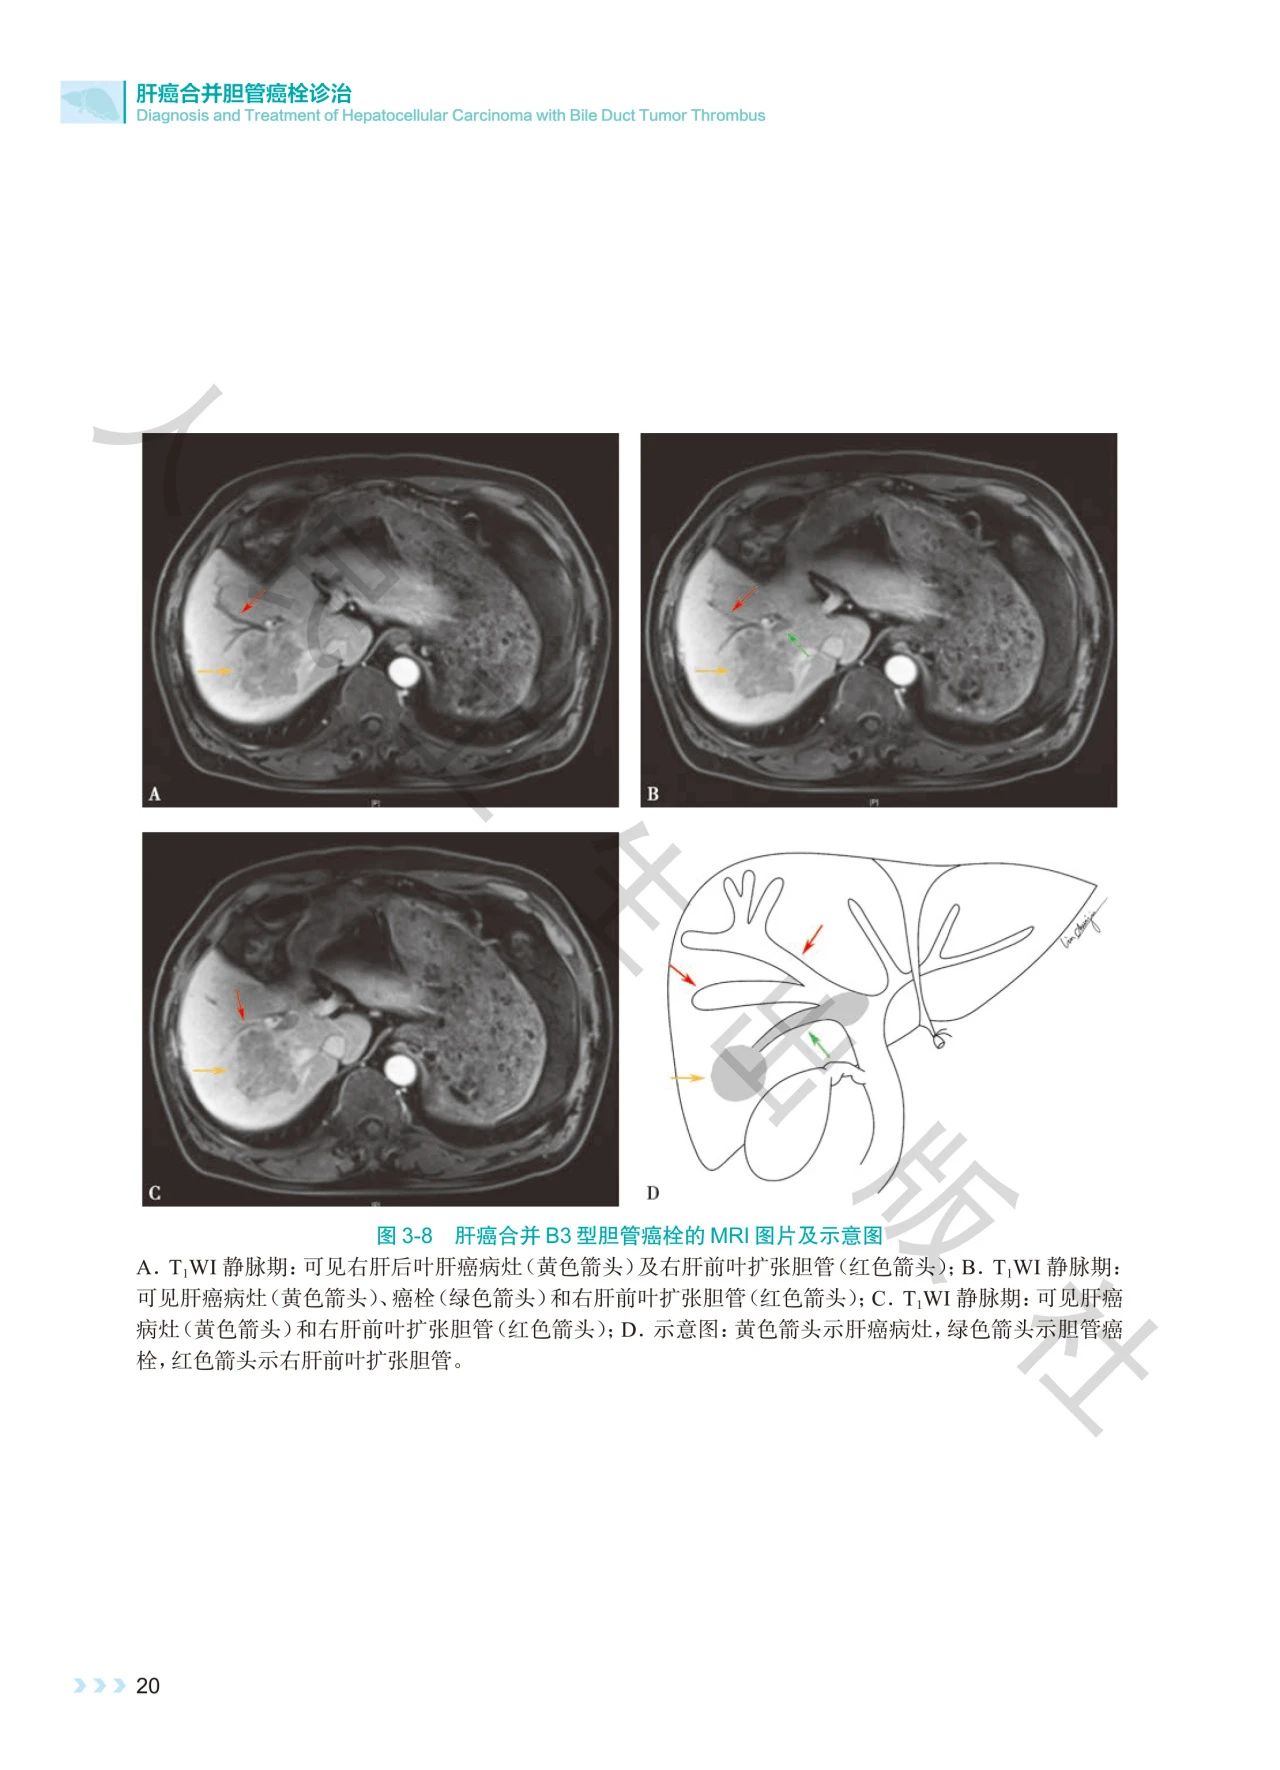

《肝癌合并胆管癌栓诊治》深入探讨了肝癌合并胆管

癌栓诊治领域的焦点问题。书中通过影像图、示意图

、手术图,详细阐述了不同分型胆管癌栓的影像学特

点及手术方式,提出q形胆总管切开取栓方法,强调解

本书通过丰富的示意图、影像图和手术图,对肝癌合

并胆管癌栓的分型、诊断策略、治疗方法等进行了深

入剖析,全面系统地总结了肝癌合并胆管癌栓领域的

前沿理论与临床实践经验。内容科学严谨、实用性强